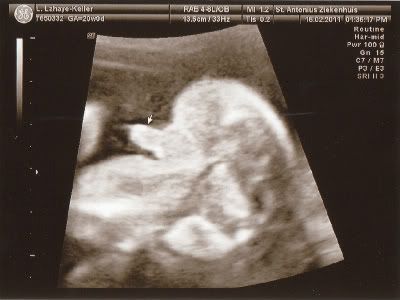

Lijkt me duidelijk wat het wordt hahahahaha.....!!!

Voor degene die niet zo goed in echo's zijn......

We gaan straks beschuit met blauwe muisjes smeren!